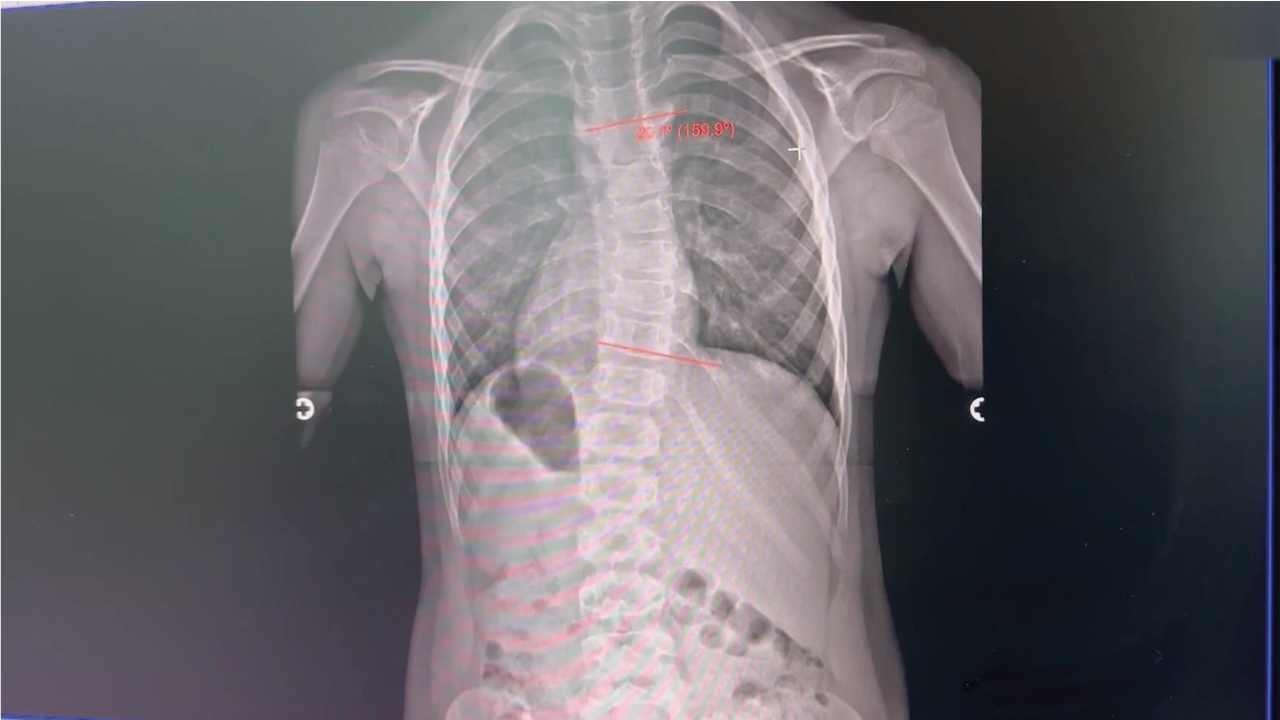

Pediatric Scoliosis and Treatment

Noticing something abnormal in your child can be alarming but conditions like scoliosis are common and early detection can help your child thrive later in life.

We learn more from Dr. John Wiemann, orthopedic surgeon with University Orthopedic Associates to learn more about pediatric scoliosis and what treatments he’s using to help pediatric patient Jolene.